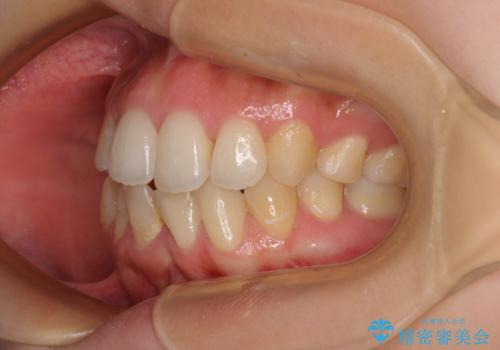

後戻りの再矯正 ワイヤー装置でデコボコと隙間を改善

- 学生時代の抜歯矯正の後戻りが気になり、再矯正を希望して来院された患者様です。

マウスピース矯正は継続する自信がなく、気になるところを短期間で改善したいとのことで、ワイヤー装置にて矯正治療を行うこととしました。

詰め物で隠していた下顎前歯の隙間は、歯軸を改善することで詰め物を除去しても隙間が目立たなくなりました。

まだ改善したいところはありましたが、患者様自身は大変満足されたとのことで、治療を終えることとなりました。